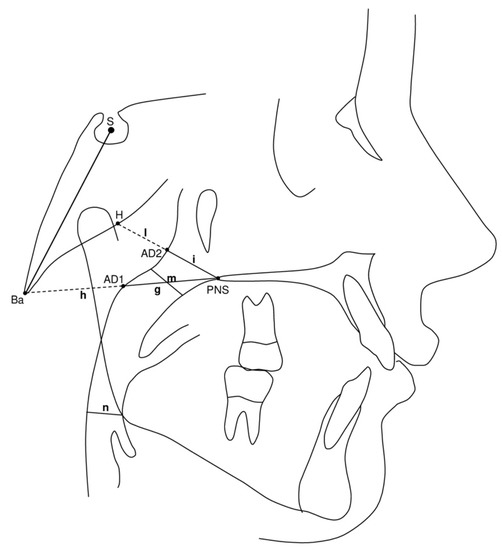

- PNS-AD1 (mm): lower airway dimension; distance between the PNS and the nearest adenoid tissue measured through the PNS-Ba line (AD1) (Figure 3, g);

- AD1-Ba (mm): lower adenoid size; defined as the soft tissue thickness at the posterior nasopharynx wall through the PNS-Ba line (Figure 3, h);

- PNS-AD2 (mm): upper airway dimension; distance between the PNS and the nearest adenoid tissue measured through a perpendicular line to S-Ba from PNS (AD2) (Figure 3, i);

- AD2-H (mm): upper adenoid size; defined as the soft tissue thickness at the posterior nasopharynx wall through the PNS-H line (H, Hormion, point located at the intersection between the perpendicular line to S-Ba from PNS and the cranial base) (Figure 3, I);

- McNamara’s upper pharynx dimension (mm): the minimum distance between the upper soft palate and the nearest point on the posterior pharynx wall (Figure 3, m);

- McNamara’s lower pharynx dimension (mm): the minimum distance between the point where the posterior tongue contour crosses the mandible and the nearest point on the posterior pharynx wall (Figure 3, n).